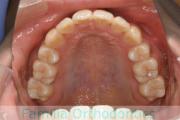

No.19V-051

- 主な症状:

- 叢生

- 年齢:

- 13歳

- 性別:

- 男性

- 抜歯部位

- 上:

- 55

- 主な使用装置:

- FEA

- 治療にかかった費用:

- 90万円

犬歯が八の字になっているので何とかしてほしいということで来院されました。上顎犬歯が左右とも前歯の方に向いていて、一期治療でまずは萌出誘導を行いました。

二期治療は、出っ歯の要素が強かったため、上顎のみ第二小臼歯を抜歯しています。

二期治療は2年強、25回程度の通院が必要でした。犬歯の埋伏歯は、うまく出すことができない場合があったり、出す際に周囲の歯の歯根に傷をつけるリスクがあったりします。

- ≫治療前

-

上顎

下顎